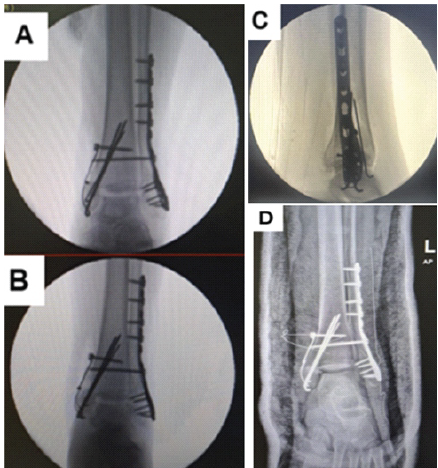

The patient was admitted under the orthopedic and trauma surgery team, kept nil per os, and started on analgesics and intravenous cefuroxime due to leukocytosis noted on complete blood count. A plan was made to perform surgical fixation the following day. The patient underwent open reduction and internal fixation the next day. Using a lateral ankle approach, the fibular fracture site was exposed, and callus from previous injury was debrided. Intraoperative findings suggest that the syndesmotic injury is chronic, with evident ligament fraying and fibrotic tissue consistent with longstanding instability. A disrupted syndesmosis with shortening of the distal fibula was confirmed. Reduction was performed and secured using a lateral plate with multiple screws, and a single 3.5 mm quadricortical syndesmotic screw was inserted under fluoroscopic guidance (Fig. 3).

Figure 3: Fluoroscopic images showing initial single 4-cortex syndesmotic screw fixation following open reduction with internal fixation. Mortise (a), Anteroposterior (b), and Lateral (c) views. (d) Post-operative X-ray showing bimalleolar fixation with a single syndesmotic screw in situ.